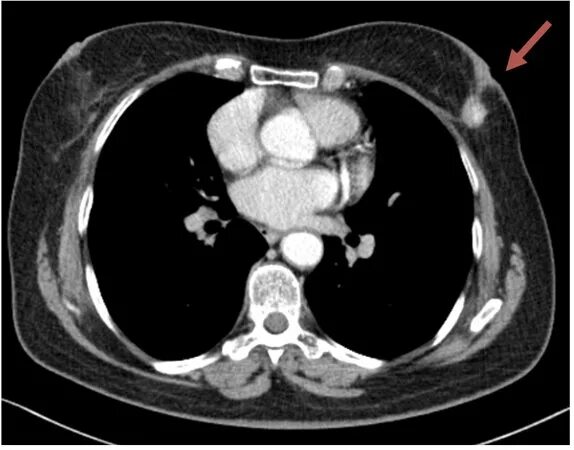

Делают ли кт молочных желез